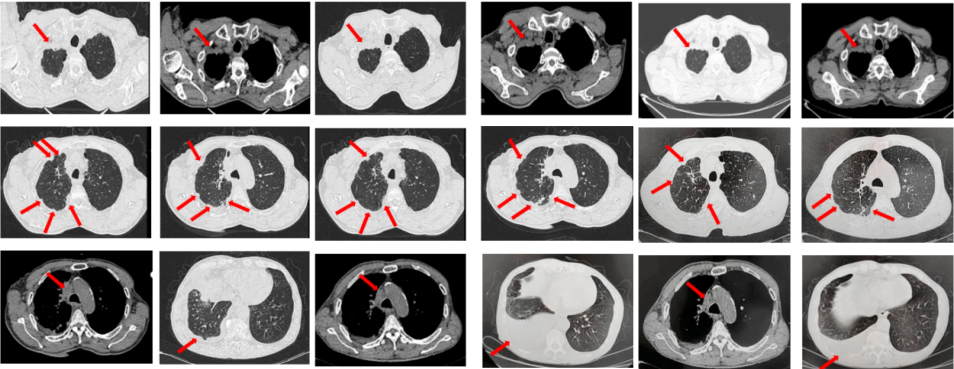

2023年9月复查评效PD。成功入组“一项开放、多中心对比谷美替尼与多西他赛在既往接受免疫治疗和含铂双药化疗后进展的驱动基因阴性且伴有MET扩增的局部晚期或转移性非小细胞肺癌患者中的随机对照III期临床研究”。成功随机到试验组,口服谷美替尼至2024年10月,期间复查最佳评效PR。

图3:A.二线治疗后病情进展,右肺上叶新发肿物较前明显增大,新发无症状脑转移病灶;B.经谷美替尼(300mg po qd)治疗3个月后复查肺内病灶及颅内病灶较前明显缓解

67岁女性患者,无既往病史。2019年10月患者因右侧季肋部不适行肺CT提示右肺中叶改变,双肺结节,右侧胸腔积液。行右侧胸腔穿刺引流,送检胸腔积液,液基薄层结果提示肺腺癌。确诊为右肺中叶恶性肿瘤cT2bN1M1a IVA期。基因检测(胸腔积液):EGFR L858R突变。建议患者口服奥希替尼,患者拒绝。2019年11月始口服埃克替尼,定期复查,最佳评效PR(图5)。

图5:A.第2例患者的基线影像资料,由上至下依次为右肺肿物、双肺转移灶及右侧胸腔积液;B.EGFR-TKI一线治疗后最佳复查评效,肺内病灶较前缩小,胸腔积液较前明显吸收。

2020年11月复查评效PD。复测基因检测(血检):T790M阳性,改行奥希替尼治疗,期间评效均为SD(图6)。

图6:A.埃克替尼靶向治疗后病情进展,肺内病灶较前增大,右肺近胸膜处新发转移灶;B.更换三代EGFR-TKI治疗后复查多处病灶未见明显变化。